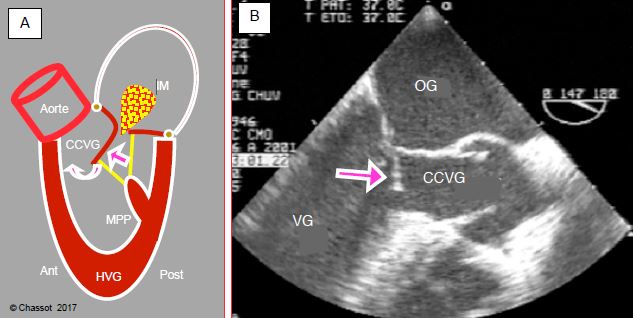

L'hypovolémie est parfois associée à un phénomène qu'il n'est possible de diagnostiquer que par échocardiogaphie: il s'agit de l'obstruction dynamique de la chambre de chasse sous-aortique, appelée fréquemment "effet CMO" par analogie avec la cardiomyopathie obstructive. Ce type de bas débit survient lorsque la cavité ventriculaire gauche diminue considérablement de volume en systole, en général sur la combinaison d'une hypovolémie avec une sur-stimulation catécholaminergique ou une vasoplégie chez un patient souffrant d'une HVG concentrique (HTA, sténose aortique, etc). Le rétrécissement de la cavité du VG déplace antérieurement la paroi postérieure et le point de coaptation de la valve mitrale, laissant la partie distale du feuillet mitral antérieur libre dans la cavité gauche (Figure 6.44) [5].

Figure 6.44: Contraction du VG. A : Situation normale. L’augmentation de la pression intra-ventriculaire en systole applique les deux feuillets de la valve mitrale l’un contre l’autre (flèches violettes) ; la contraction de la paroi et des muscles papillaires (MPA : muscles papillaire antérieur, MPP : muscle papillaire postérieur) tend les cordages et maintient la valve mitrale dans son plan d’occlusion (flèches vertes). Ceci constitue le squelette interne du ventricule. Le sang est expulsé dans la chambre de chasse du VG (CCVG). La contraction débute à l’apex et se termine dans la chambre de chasse. B : Rétrécissement de la cavité ventriculaire. Si la course de la paroi postérieure et du MPP est trop longue (surstimulation β, vasoplégie) ou si le ventricule est trop petit (hypovolémie, hypertrophie concentrique), la paroi postérieure se déplace vers l’avant (flèche verte) ; le point de coaptation de la valve mitrale est déplacé antérieurement vers l’aorte et se rapproche de la CCVG. Le feuillet antérieur est alors repoussé vers la CCVG lorsque la pression intraventriculaire augmente pendant la systole (flèche violette). Traitillé blanc : angle mitro-aortique. L’angle mitro-aortique est un point fixe puisqu’il est situé au niveau du trigone fibreux, qui est le centre de gravité mécanique du cœur sur lequel sont ancrées les valves mitrale, aortique et tricuspide. Si l’anneau mitral se rétrécit, le seul déplacement possible est celui de sa partie postérieure, qui est essentiellement musculaire, et qui se retrouve alors tirée vers l’avant.

En cours de systole, la partie distale du feuillet mitral antérieur est poussée vers la chambre de chasse du VG (CCVG) par la montée de pression dans le VG et par le début de l'éjection vers l'aorte. Elle est secondairement aspirée par effet Venturi dans la CCVG qu'elle vient obstruer partiellement (SAM: systolic anterior motion) (Figure 6.45) [11].

Figure 6.45: Effet CMO en cas de restriction de la cavité ventriculaire gauche et d’avancement excessif de la paroi postérieure. A : la pression de la phase de contraction ventriculaire pousse le feuillet vers l’avant en direction de la CCVG. Dès que l’éjection commence, la partie distale de ce feuillet peut être aspirée dans la CCVG par effet Venturi et induire un phénomène appelé systolic anterior motion (SAM). Le feuillet antérieur vient alors occlure partiellement la CCVG et le débit systolique baisse brusquement. C’est l’effet CMO, appelé ainsi par analogie avec le mécanisme de la cardiomyopathie obstructive. La réouverture de la valve mitrale en mésosystole provoque une insuffisance mitrale méso-télésystolique (IM). B : illustration échocardiographique transoesophagienne (vue mi-œsophage long-axe 120°) ; la flèche indique la coudure du feuillet mitral antérieur (SAM) qui vient obstruer la chambre de chasse gauche (CCVG). Les cuspides de la valve aortique sont ouvertes.

Cette subobstruction entraîne deux effets: la vélocité maximale du sang dans la CCVG augmente > 2.5 m/s (valeur normale: 1 m/s), et le volume systolique s'effondre car le rétrécissement limite le passage du sang. Cliniquement, l'effet CMO se caractérise par une hypotension artérielle, une tachycardie et un bas débit cardiaque qui s’aggravent avec les catécholamines, mais des pressions de remplissage conservées, voire élevées [20]. Le seul traitement est une augmentation de la volémie (remplissage), une vasoconstriction (phényléphrine, noradrénaline) et une diminution de l'effet β (arrêt des catécholamines, esmolol).